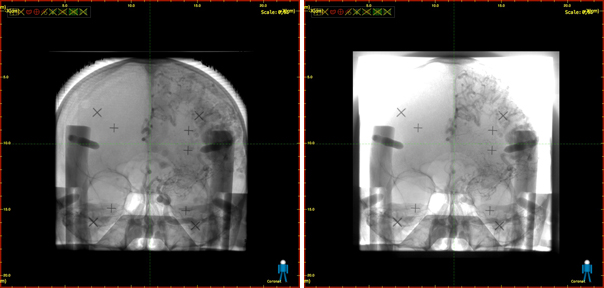

Mejora del contraste obtenida en la imagen de un cráneo mediante la nueva tecnología (izquierda) frente a imagen convencional (derecha)./ CSIC

En diagnóstico clínico, este tipo de imagen incorpora información de la fisonomía del paciente, facilita la interpretación de la imagen y ayuda en la decisión del radiólogo, agilizando el diagnóstico. Esta mejoría en la calidad de la imagen se produce por medio de una corrección espacial, y no por medio de filtros matemáticos que podrían inducir a errores en la interpretación de lesiones. El sistema también permite cuantificar de forma más precisa la absorción en sistemas calibrados y parametrizar los valores de absorción obtenidos en función del espesor del material.